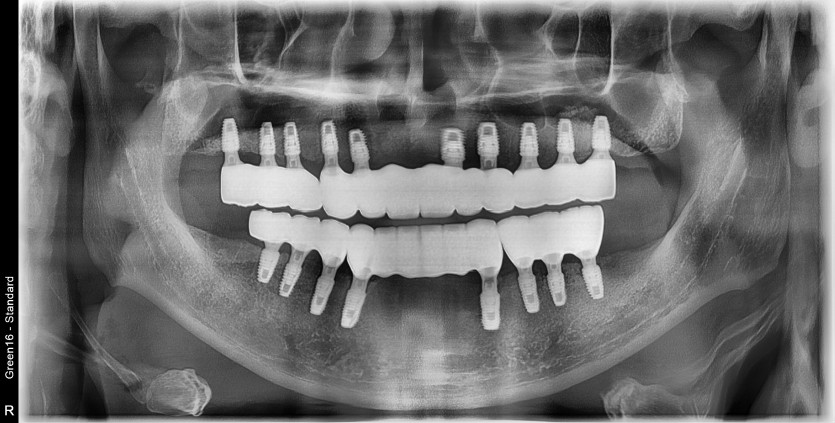

전체 임플란트 증례입니다.

18개의 임플란트로 완성하였습니다.